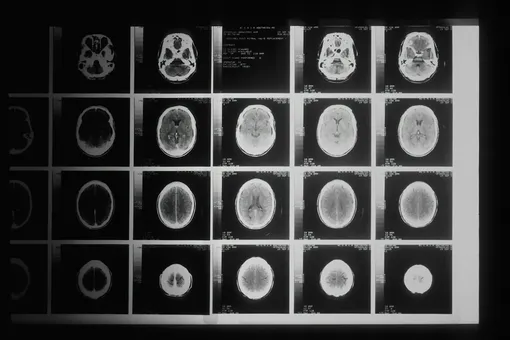

Как сообщает портал Gizmodo, в конце декабря в Великобритании умер 24-летний Андре Ярхам (Andre Yarham). Причиной стала ранняя форма лобно-височной деменции – заболевания, которое обычно диагностируют людям в возрасте от 45 до 65 лет. В случае Ярхама болезнь проявилась настолько рано, что его мозг по результатам МРТ выглядел как у пожилого человека.

Первые тревожные симптомы появились в конце 2022 года. Он стал забывчивым, его поведение начало меняться. Обследования выявили уменьшение объема мозга, особенно в зонах, отвечающих за речь, мышление и личность.